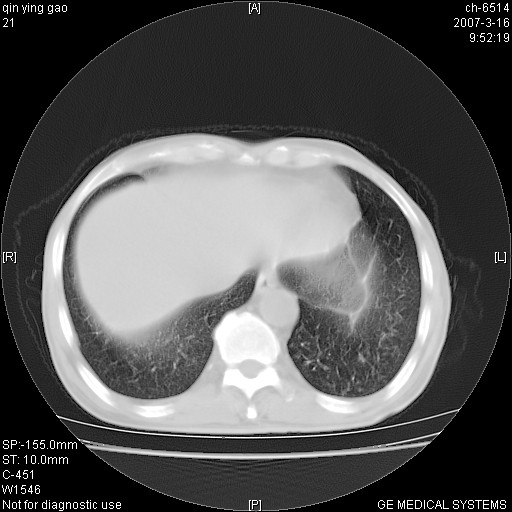

男,64岁.乏力2个月,畏寒、发热1月余。体重下降。血沉加快,白细胞不高。

两肺弥漫分布的斑片状影,部分融合,左肺及纵隔淋巴结见钙化影,考虑1。tb,2。肺泡细胞癌,建议查痰检

两肺弥漫分布的斑片状影,部分融合,主要集中中上肺.考虑1、结核?2、非特异性炎症

两中上肺见有广泛分布大小不一的结节灶及斑片状影,部分融合,双下肺未见异常密度影,纵隔无明显肿大淋巴结,血沉加快,白细胞不高,首先考虑结核。 建议结合ppd检查或痰培养排除其他非特异性炎症。